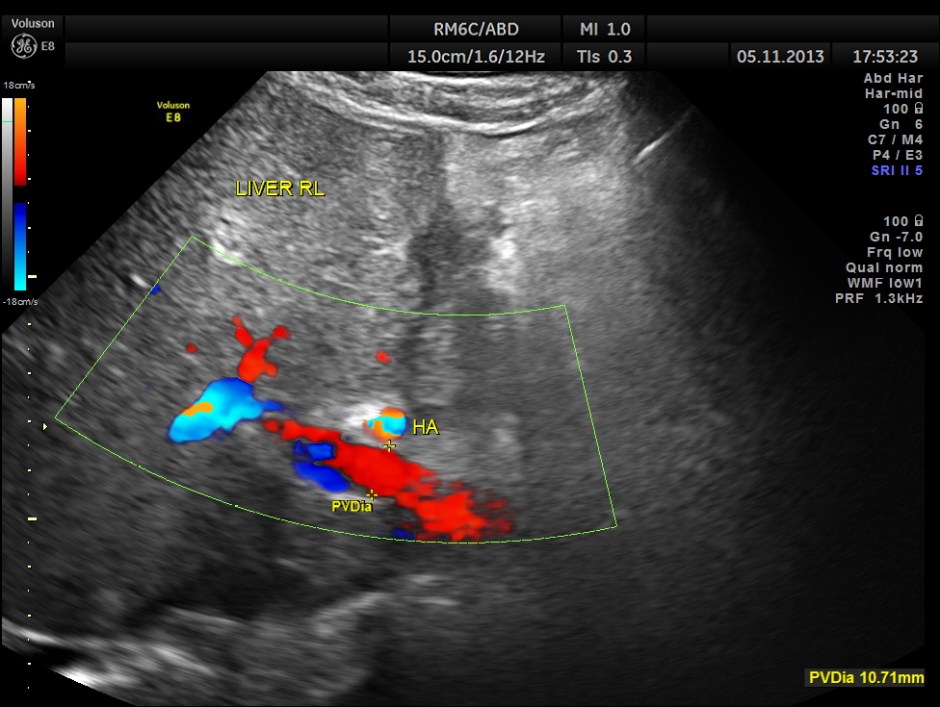

Colour flow mapping shows non visualisation of Common Bile Duct consistent with history.

This patient had a painful metastatic nodule in the right lobe of the liver. He also had loculated sub diaphragmatic collection and a septated cystic mass in the free surface of the liver.